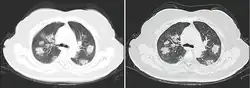

Imaging

Chest CT scans may be helpful to diagnose COVID‑19 in individuals with a high clinical suspicion of infection but are not recommended for routine screening.[175][187] Bilateral multilobar ground-glass opacities with a peripheral, asymmetric, and posterior distribution are common in early infection.[175][188] Subpleural dominance, crazy paving (lobular septal thickening with variable alveolar filling), and consolidation may appear as the disease progresses.[175][189] Characteristic imaging features on chest radiographs and computed tomography (CT) of people who are symptomatic include asymmetric peripheral ground-glass opacities without pleural effusions.[190]

Many groups have created COVID‑19 datasets that include imagery such as the Italian Radiological Society which has compiled an international online database of imaging findings for confirmed cases.[191] Due to overlap with other infections such as adenovirus, imaging without confirmation by rRT-PCR is of limited specificity in identifying COVID‑19.[190] A large study in China compared chest CT results to PCR and demonstrated that though imaging is less specific for the infection, it is faster and more sensitive.[174]

By a variety of mechanisms, the lungs are the organs most affected in COVID‑19.[332] In people requiring hospital admission, up to 98% of CT scans performed show lung abnormalities after 28 days of illness even if they had clinically improved.[333] People with advanced age, severe disease, prolonged ICU stays, or who smoke are more likely to have long-lasting effects, including pulmonary fibrosis.[334] Overall, approximately one-third of those investigated after four weeks will have findings of pulmonary fibrosis or reduced lung function as measured by DLCO, even in asymptomatic people, but with the suggestion of continuing improvement with the passing of more time.[332] After severe disease, lung function can take anywhere from three months to a year or more to return to previous levels.[335]